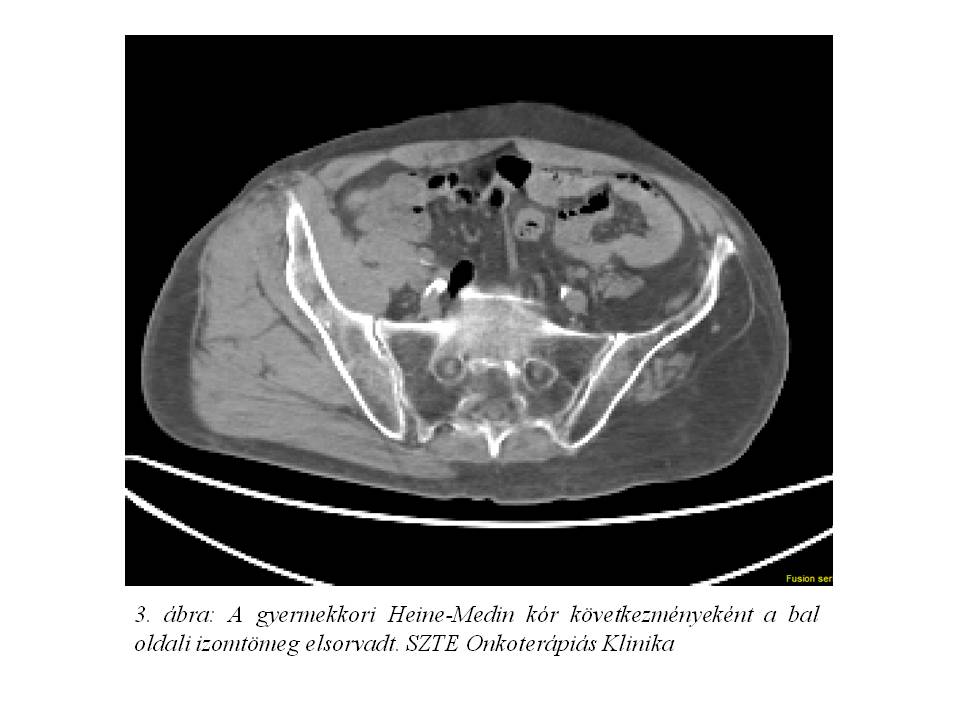

Kórtörténetéből a gyermekkori Heine-Medin kór (3. ábra) emelhető ki, mely miatt jelenleg is izomlazítót és alkalmanként fájdalomcsillapítót szed.